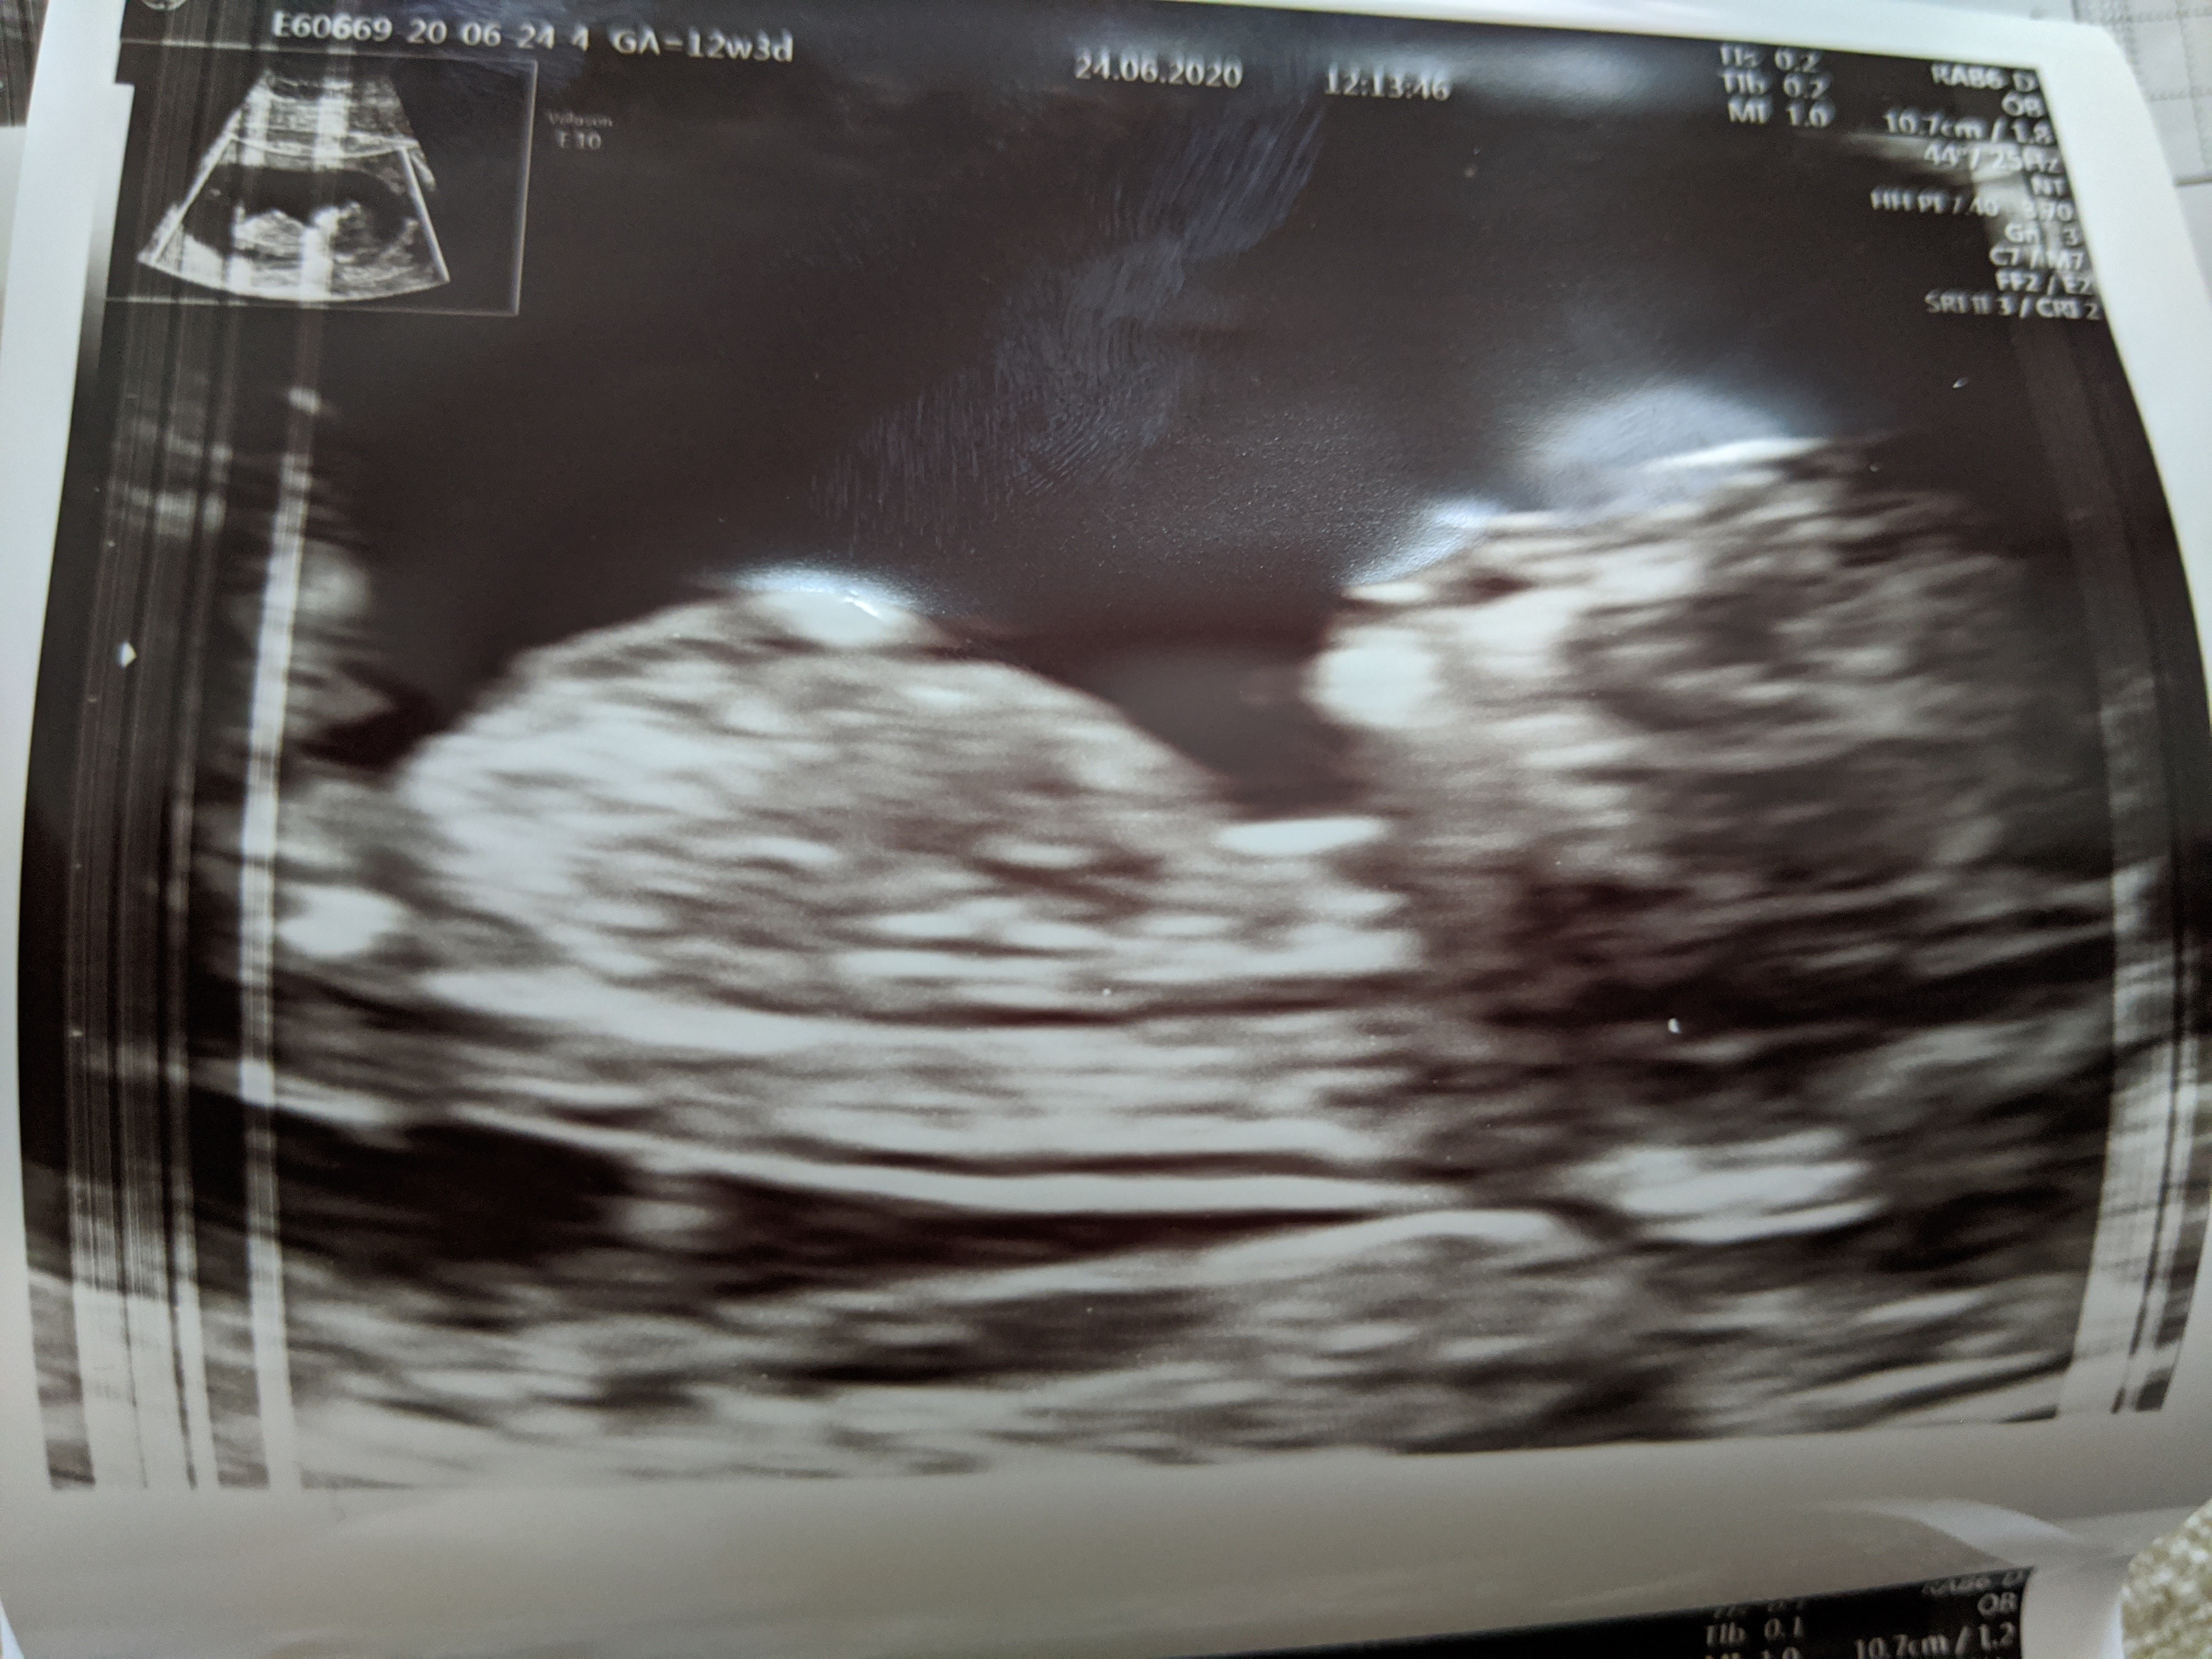

Dopiero teraz piszę bo zabrałam tatusia na pizzę i ciasto po badaniach bo niestety nie mógł wejść ze mną ale dostałam całe badanie na płytce, za chwilę oglądamy 😁

Dzidziuś jest zdrowy, żadnych wad na usg nie było widać. Jutro robię PAPPA bo podobno wskazane dla kobiet u których USG wyszło dobrze. Ale mi ulżyło dziewczyny, to był dla mnie kluczowy moment, żeby dowiedzieć się czy dziecię jest zdrowe.

Niestety nie chciał pokazać co tam ma między nogami ale najważniejsze, że zdrowe🙂 Zobacz załącznik 1138499